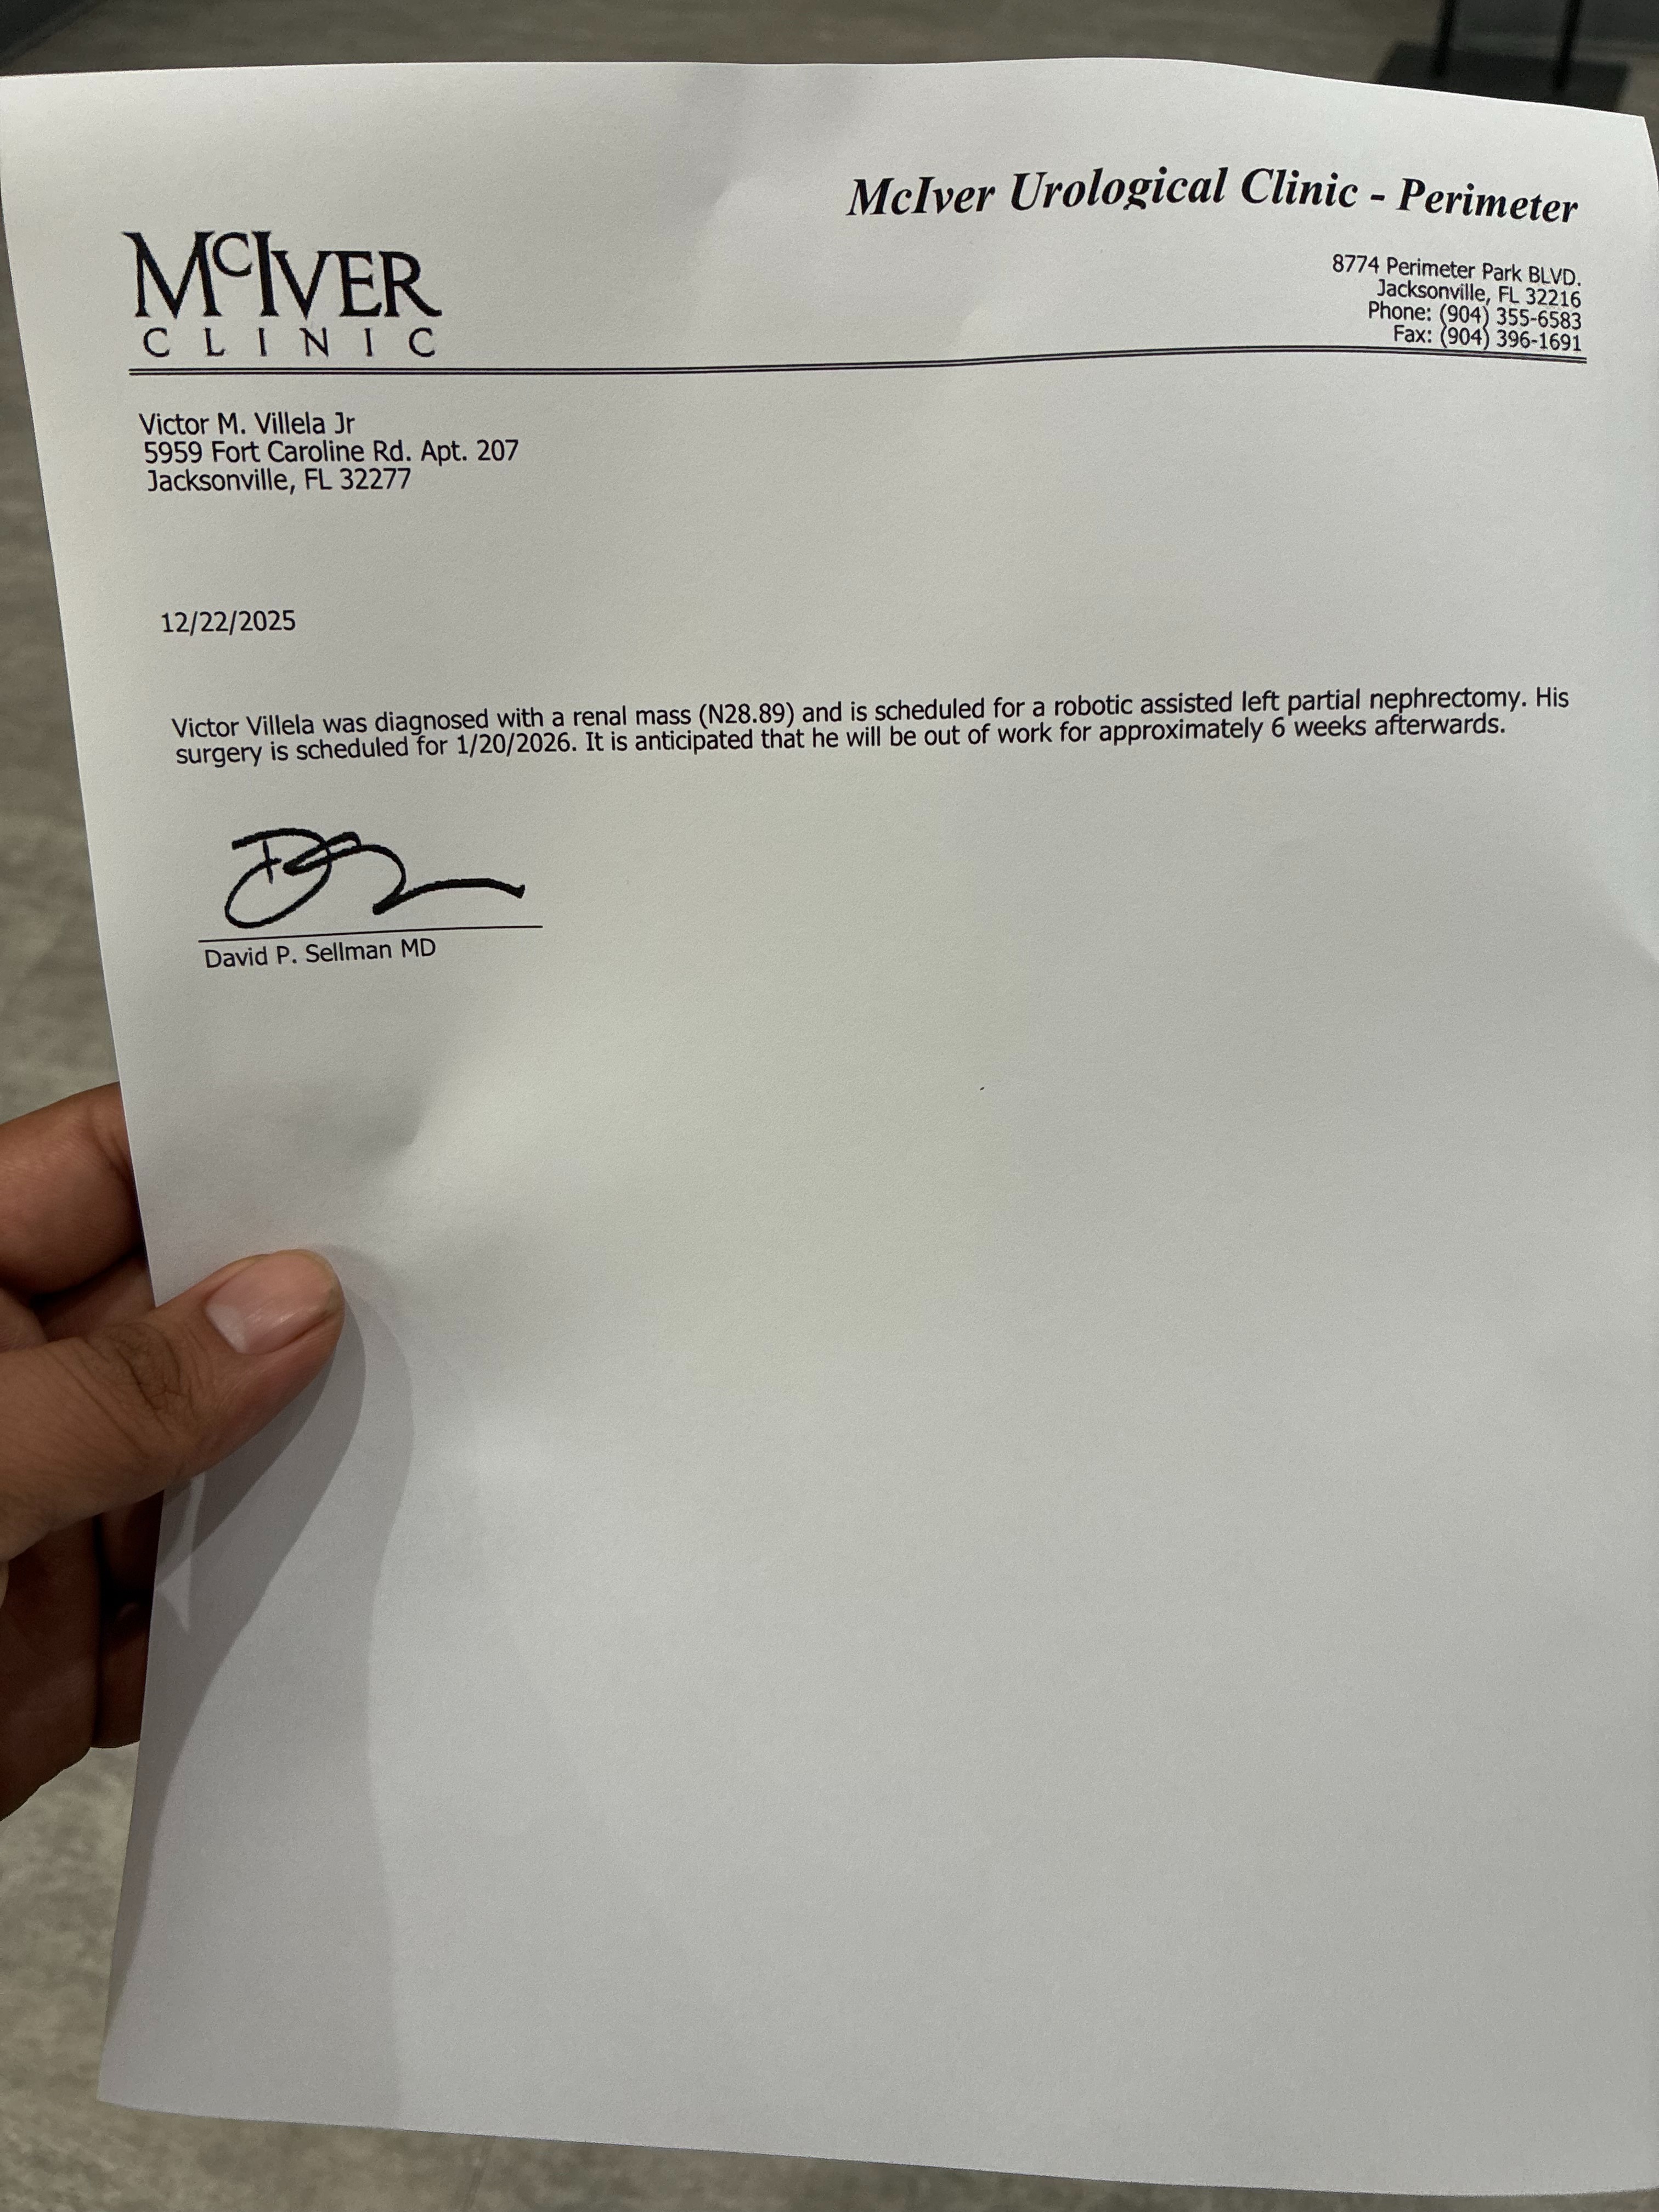

Recently, Victor suffered a fall from a second-story level while at work. During his ER visit, doctors discovered a mass in his kidney. They are 85% certain it is cancerous, and Victor is scheduled for surgery on January 20, 2026. The recovery is expected to take at least six weeks, during which he will not receive any pay. As a stay-at-home mom, I will also be recovering from a c-section after our baby arrives on February 23, 2026, and Victor will need to take unpaid paternity leave to care for our family.

Recently, Victor suffered a fall from a second-story level while at work. During his ER visit, doctors discovered a mass in his kidney. They are 85% certain it is cancerous, and Victor is scheduled for surgery on January 20, 2026. The recovery is expected to take at least six weeks, during which he will not receive any pay. As a stay-at-home mom, I will also be recovering from a c-section after our baby arrives on February 23, 2026, and Victor will need to take unpaid paternity leave to care for our family.